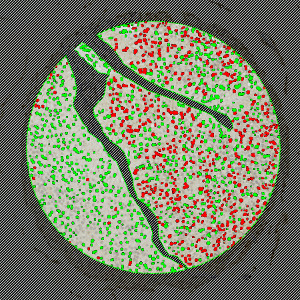

Image of a TMA core with bladder tumor tissue stained by IHC for Annexin 10.

The method used for computing the Annexin 10 expression is started by detecting nuclei using a novel pattern recognition method adapted from Dahl et al , see [8], which is followed by a step that separates adjacent nuclei, see [9]. The detected nuclei are classified as either positive or negative based on a computation of DAB intensity, obtained using color de-convolution.

This leads to the calculation of the positive area fraction, as the area of positive nuclei divided by the total area of nuclei (within the outlined ROI). This is followed by the measurement of the average DAB intensity across all positive nuclei, which is subtracted from 255, to associate higher values with a high staining intensity, which is more intuitive. The expression is then calculated by multiplying the intensity with the area fraction.